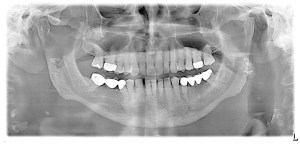

Fact: While brushing twice a day and flossing once daily is Important, it is not enough. It is also important to get routine cleanings. During cleanings, the hygienist will clean the hard to reach areas, will make sure your gums are healthy, and will educate patients on proper home care. Dentists will also use x-rays and visual exams to make sure a patient doesn’t have any problems with their teeth or gums. Many don’t know this, but you don’t always have tooth pain when you have a tooth problem or gum disease, and if left untreated a tooth problem and unhealthy gum tissue will only get worse and lead to more serious problems. That’s why it is so important to come in for routine check-ups.